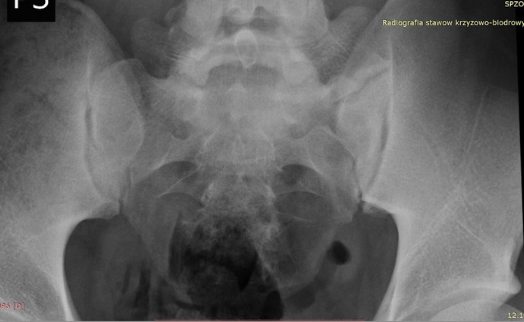

Między wyrostkiem kręgu L5 a kością krzyżową wytworzył się u niego dodatkowy staw poprzeczno-krzyżowy (typ 2a wg klasyfikacji Castellviego). Staw ten posiadał cechy stawu nieprawdziwego, czyli bez chrząstki, a więc występowało bolesne ocieranie kości o kość, utrudniające normalne funkcjonowanie.

W badaniach radiologicznych (zdjęcia rentgenowskie, tomograf komputerowy) uwidocznioną tę patologię, widać również obrzęk tych kontaktujących ze sobą powierzchni.